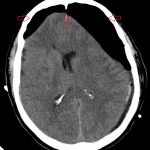

Huyết khối tĩnh mạch não (Cerebral Venous Thrombosis) là hiện tượng hình thành các cục máu đông trong các tĩnh mạch và xoang tĩnh mạch của não, chiếm tỷ lệ 0.5-1% tổng số những trường hợp đột quỵ. Trong tổng số các trường hợp xuất huyết não ở người trẻ, huyết khối xoang tĩnh mạch chiếm 5%…